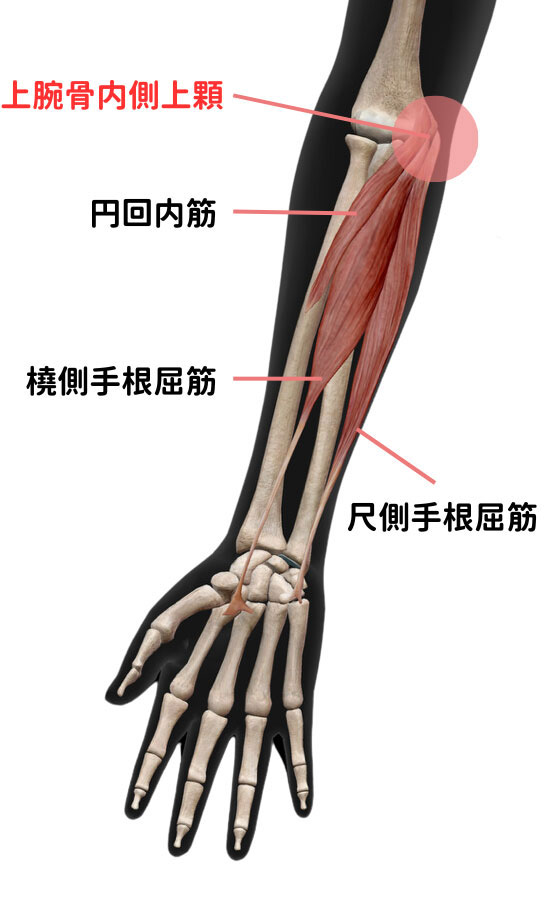

The pain is caused by damage or inflammation of the tendons of the pronator teres and the wrist flexor muscles (including the flexor carpi radialis and flexor carpi ulnaris) that attach to the inner part of the elbow (the medial epicondyle of the humerus).